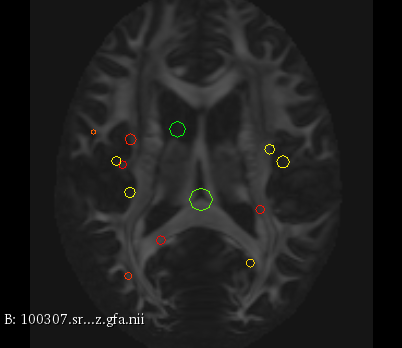

Figure 3 provides a scale-space visualization of feature matches for a single pair of MZ twins and NT siblings, where scale information is represented using the circle radius. Note that circles represent the intersection of 3D spheres with the visible slice and, thus, non-intersecting features are hidden in this 2D visualization.

It can be seen that different image modalities generally result in distinct, complementary feature correspondences throughout the brain, allowing a rich characterization of both anatomical and connectivity structure. In T1 and T2 images, features are mainly located in the frontal lobe, corpus callosum and brain stem. Smaller-scale features are also visible along various cortical regions, as well as in sub-cortical structures near the basal ganglia. Although highly correlated, T1 images show significantly more feature matches than T2 images. Moreover, images based on diffusion measures have less matches than in structural modalities. These matches are located mostly inside or near to white matter: larger-scale features in the corpus-callosum, and smaller-scale ones in the brain stem and along white matter bundles. While not shown in the figure, the set of matches found by combining two modalities (e.g., T1 + T2) generally corresponds to the union of those obtained with these individual modalities.

Comparing different sibling types, we observe a greater number of matches between MZ twins than NT siblings. This observation, which is easier to visualize in T2 and GFA images, is consistent with other analyses on twin datasets. In terms of feature location and scale, no obvious pattern can be seen when comparing these two sibling types. However, a more detailed analysis would be required to validate this assertion.